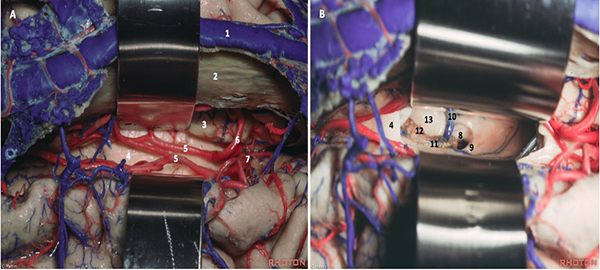

Durotomía arciforme con base al SSS, respetando componentes venosos que suelen encontrarse. Aunque estas estructuras de drenaje a lo largo del tercio anterior del SSS se consideran seguras de ligar, el riesgo de infarto venoso está descripto de forma predominante cuando son voluminosas y no hay venas suplementarias que drenen el determinado sector. En consecuencia, su manipulación y sacrificio deben mantenerse al mínimo. Se realizó drenaje del líquido cefalorraquídeo (LCR) mediante punción lumbar aproximadamente 12 cc para descomprimir el parénquima y favorecer la separación. Los retractores fijos se tratan de evitar mediante el uso de retracción dinámica, intermitente e inducida por la gravedad (rotación de la cabeza de forma que el seno sagital se posicione paralelo al suelo, o colocar al paciente en decúbito lateral). Una vez identificado el lugar apropiado para acceder a la fisura interhemisférica, comienza su disección con técnica microquirúrgica y utilizando microscopio (Leica M525 OH4), se procede a la apertura de la aracnoides con microtijera en sentido longitudinal, debiendo reconocer la circunvolución frontal superior lateralmente y el borde libre de la hoz del cerebro, inmediatamente después encontrándose la circunvolución del cíngulo. La neuronavegación permite localizar sin dificultad al cuerpo calloso, disminuyendo el tiempo quirúrgico. Puede a su vez distinguirse por el color blanco nacarado, avascular y con las arterias pericallosas sobre su cara superior, las cuales se disecan por la línea media exponiéndolo (Figura 4A). En ocasiones, éstas pueden desplazarse hacia lateral o adherirse, lo que dificulta su separación con riesgo de lesionarlas.9 La callosotomía se realiza en el tercio anterior, en sentido anteroposterior con coagulación bipolar y tijera microquirúrgica, no debiendo exceder de 20 mm, lo cual proporciona adecuada visualización del foramen de Monro, las venas cerebrales internas, coroideas y talamoestriadas.10 11 12 Esta apertura limitada generalmente no implica secuelas neuropsicológicas postoperatorias (Figura 4B-5).

Figura 4. Anatomía quirúrgica de la cisura interhemisférica (A) y posterior a callosotomía (B): seno sagital superior (1); hoz del cerebro (2); circunvolución del cíngulo (3); cuerpo calloso (4); arteria pericallosa (5) y callosomarginal (6); arteria cerebral anterior (7); foramen de Monro (8); pilar del fórnix (9); vena talamoestriada (10); vena coroidea (11); plexo coroideo (12); tálamo (13). Adaptado de: The Rhoton Collection®33